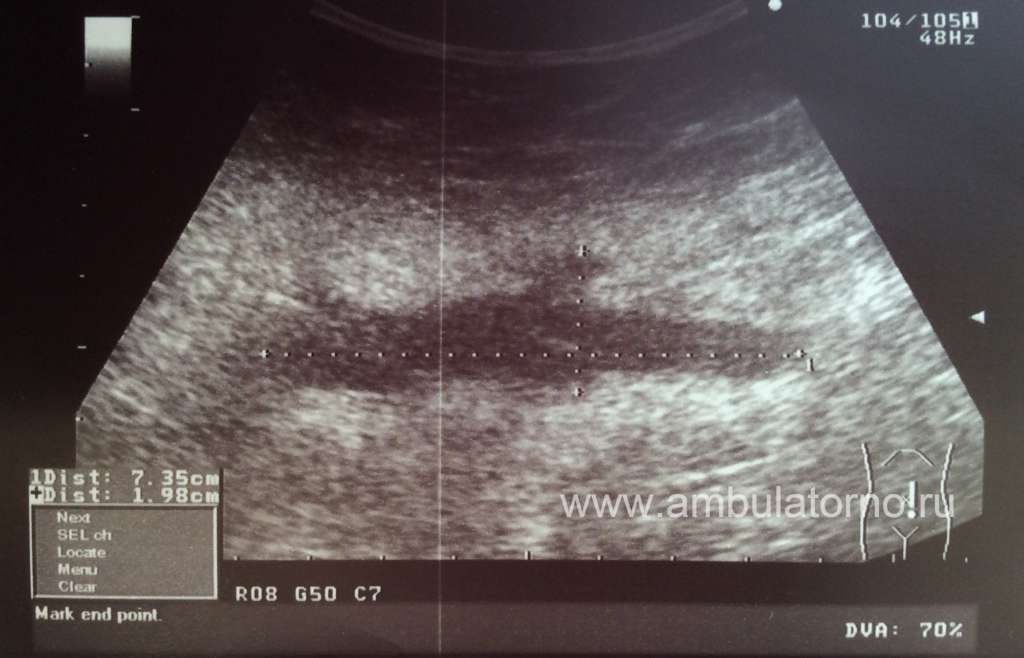

Пациентка И., 57 лет. Диагноз: ПМЗО: рак прямой кишки. Состояние после комбинированного лечения в 2008 году. Рак правой молочной железы T2N0M0, IIa ст. Хирургическое лечение: кожесохранная радикальная мастэктомия справа с сохранением грудных мышц с одномоментной реконструкцией торакодорзальным лоскутом. На протяжении 8 месяцев после оперативного лечения, пациентка в амбулаторном порядке 3 раза в неделю посещала отделение для выполнения пункции серомы. За данный период времени количество эвакуируемой жидкости за каждую процедуру изменилось незначительно и составляло около 400 мл. Предпринималась попытка установки пассивного дренажа Pleurocan и одномоментное тугое компрессионное бинтование. В течение 14 дней, динамики в количестве отделяемой по дренажу жидкости не отмечено, размер полости серомы так же остался прежний. После чего Pleurocan был удален.

Спустя 2 недели начато комбинированное фармакологическое лечение серомы по следующей схеме: сандостатин 0,1 мг подкожно + эритромицин 200 мг в полость серомы.

Рис. Динамика эвакуируемой жидкости из полости серомы, мл

Таблица. Схема введения препаратов и количество эвакуированной жидкости

Из данной таблицы видно прогрессивное уменьшение эвакуированной жидкости из серомы.